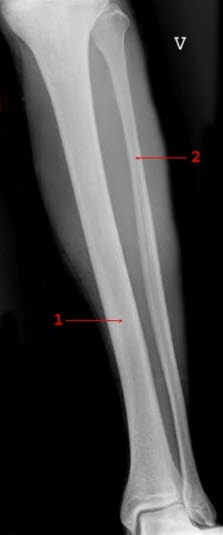

Tibia og fibulaLeggen består av to bein, skinnbeinet (tibia) og leggbeinet (fibula). Tibia er det kraftige beinet som vi ser som en skarp kant på forsiden av leggen. Fibula befinner seg på yttersiden av leggen og kjennes lett like nedenfor kneet. Begge bena inngår i kneleddet og ankelleddet. Både fibula og tibia er utsatte for brudd i kneleddet og i ankelleddet, disse bruddtypene regnes dog ikke som leggbrudd.

I et norsk sykehusmateriale som omfattet en befolkning på 180 000, ble omtrent 100 leggbrudd behandlet årlig. I tillegg behandles en del brudd som står i god stilling (ikke-dislokerte) poliklinisk og på legevakten. Brudd i leggen kan være isolerte brudd av fibula eller tibia, eller brudd som omfatter begge benene. Bruddene kan være tverr-, skrå-, spiral- eller knusnings-brudd. I tillegg kommer tretthetsbrudd og brudd på grunn av underliggende annen sykdom.

Røntgenundersøkelsen omfatter hele leggen, kneet og ankelen. Man ser etter fremmedlegemer, som kan forekomme ved åpne skader. Røntgenbildet vurderes med tanke på om bruddet kan bli stabilt uten operasjon. Særlig spiralbrudd vil ofte kreve operasjon.